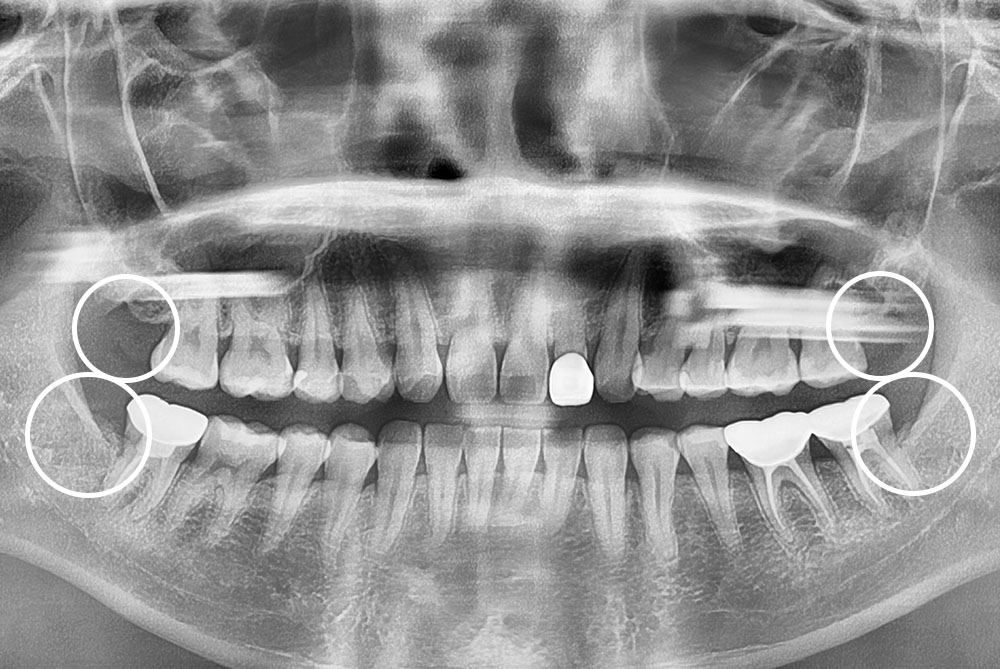

[사랑니] 매복 사랑니 발치

치료전 : 2019-02-20